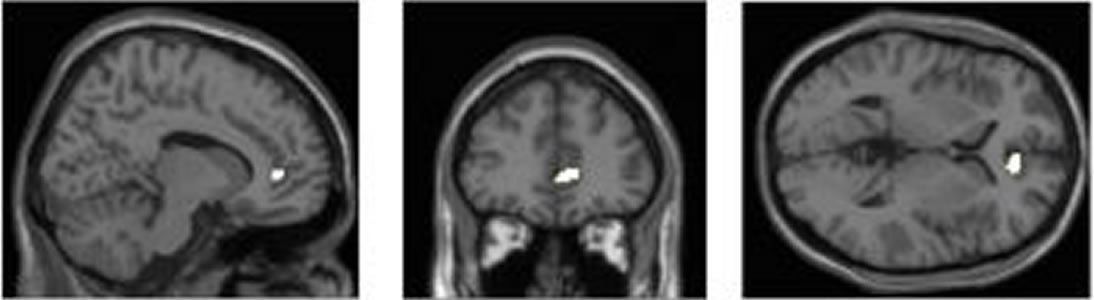

A study from the University of Sussex (UK) compared the brain structure of participants with the amount of time they spent on media devices i.e. texting or watching TV. [1]

The MRI scans of the participants, showed that the high multitaskers had less brain density in the anterior cingulate cortex. This is the brain region responsible for empathy and emotional control.

The implication of their findings, is that multitasking, especially involving the use of media devices, could permanently alter brain structure after a long period of usage.